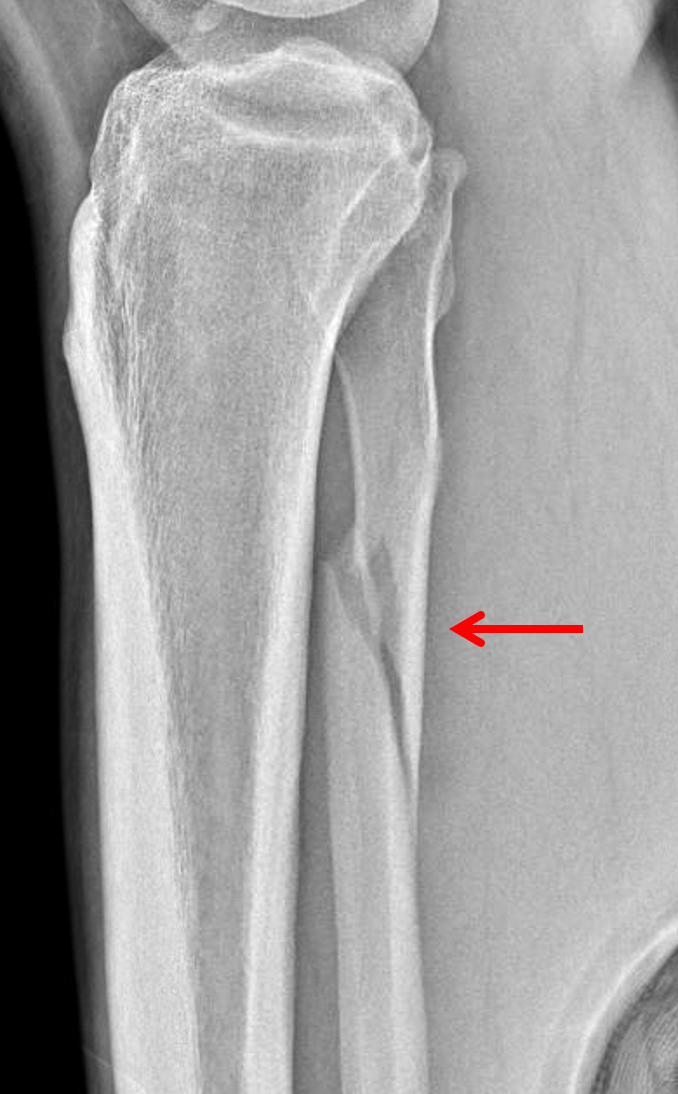

Age: 28

Sex: Male

Indication: Fall

Sample ReportMild medial clear space widening without acute fracture identified. Recommend dedicated leg radiographs to look for proximal fibular fracture.

Mild soft tissue swelling overlying the lateral malleolus.

Joint spaces are maintained.